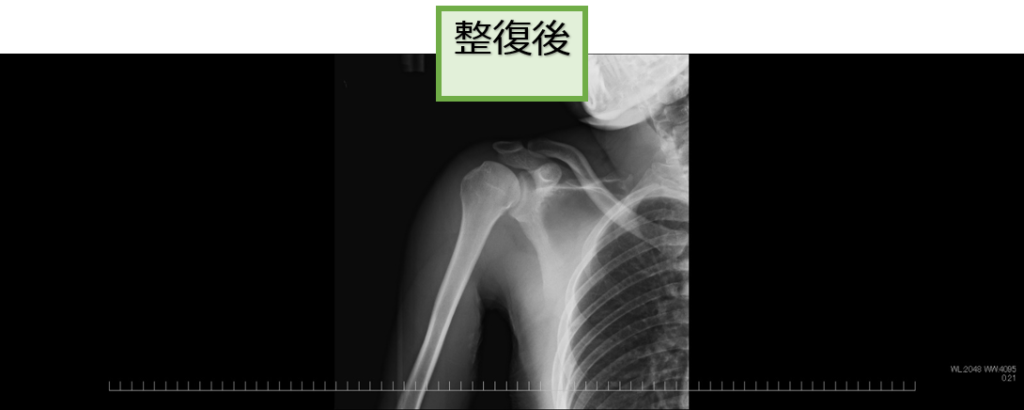

●脱臼の整復

脱臼した部分(肩や股関節など)をリアルタイムに観察しながら元の位置に戻す(整復術)治療です。この治療は整形外科医師が行います。

股関節脱臼に対する整復

右肩関節脱臼に対する整復